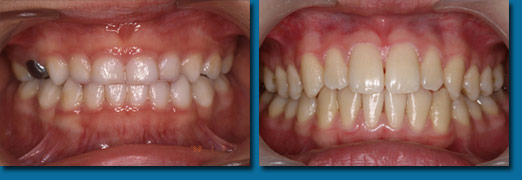

歯並びが悪くなってから治療することを歯列矯正といいますが、乳歯の頃から出てくる歯並びが悪くなる兆候を早期に発見しそれを改善しながらきれいな歯並びの永久歯にしていくことを咬合育成といいます。専門的には歯列矯正と咬合育成は別の物と区別されています。咬合育成は歯並びの予防と考えられ当医院では積極的に取り組み、多くの歯並びの良い子供が育っています。写真の左は乳歯の時、右が永久歯になった時のものです。